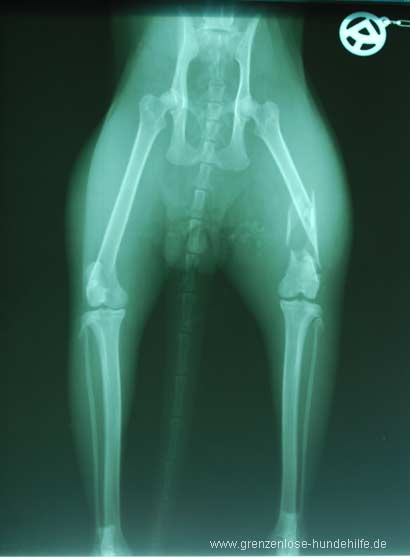

Die Röntgenbilder zeigten sofort die traurige Wahrheit: Sein rechter Hinterlauf war gebrochen, Jaloux hatte sich eine distale Femur-Splitterfraktur zugezogen, die anscheinend nicht so ganz einfach chirurgisch versorgt werden konnte.

Daher riet der Tierarzt zu einer Amputation des Beines. Diese Nachricht war ein großer Schock für uns !!!